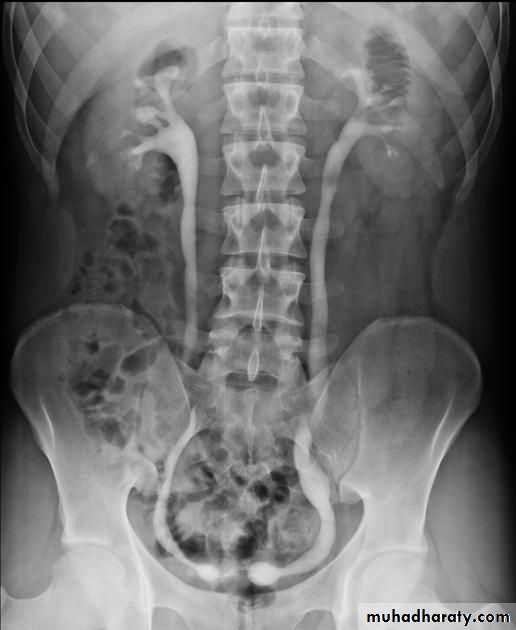

Normal IVU series

Bulb of follys cathter IVU with bilateral mild to moderate degree of HN

RT sided PUJ stenosis & obstruction with RT sided HN

Uretrocele (cobra head shape)distal both sided ureteric ends with dilated both ureters

Uretrocele